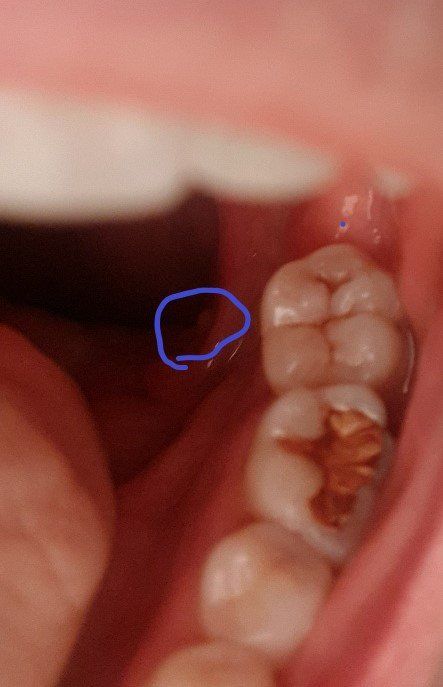

혀 제일 안쪽 옆에 뾰루지가 났어요 무엇인가요?

일주일 전부터 자꾸 혀 옆에 이물감이 들어서 혀를 최대한 밀고 보니 사진처럼

혀 제일 안쪽 옆살과 겹치는 부분에 뾰루지같은게 났더라구요

찾아보니 비슷한게 구내염 점액낭종 같은게 있는데 아프지는 않구요 이물감 때메 무지 불편합니다.

놔둬도 사라질까요 아니면 제거해야 하나요?

• 1번 째 사진

• 올리신 사진의 소견만으로는 구체적으로 해당 병변이 무엇인지 알기에는 어렵습니다. 말씀하신 것처럼 점액낭종일 수도 있으며, 유두종 등의 다른 문제일 수도 있습니다. 이비인후과에서 진료 및 정밀 검사를 받아보시는 것을 권고드립니다.

사진만 봐서는 정확히 무엇인지 알기 어렵습니다.

증상이 지속되는 경우에는 가까운 치과 내원하여 진료 받아보시기 바랍니다.

사진만 봐서는 잘 판별이 되지 않습니다.

이비인후과 방문하셔서 정확한 진단을 받으시고 절제 필요성을 확인하시는게 맞겠습니다.

이물감이 있다면 진료를 보시는게 맞습니다.